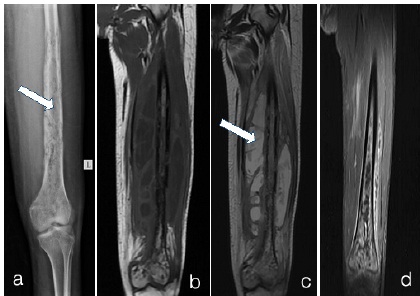

Osteomyelitis a) X-RAY LEFT LEG b)T1WI c)T2WI d)T1 fat sat + Gd

a) X-ray left leg shows multiple irregular cortical erosions in femur shaft and lower end. Extending into the medulla of femur (arrow in a). There is lamellated type of periosteal reaction.

b) and c) MRI T1WI Coronal show multiple cortical irregularities and erosions with medullary hyperintense signal in shaft and distal femur. There are multiple collections in surrounding soft tissues which appear hypointense on T1 and hyperintense on T2. (arrow in c). d) Contrast enhanced T1 fat sat image - shows enhancement in medulla and surrounding soft tissues